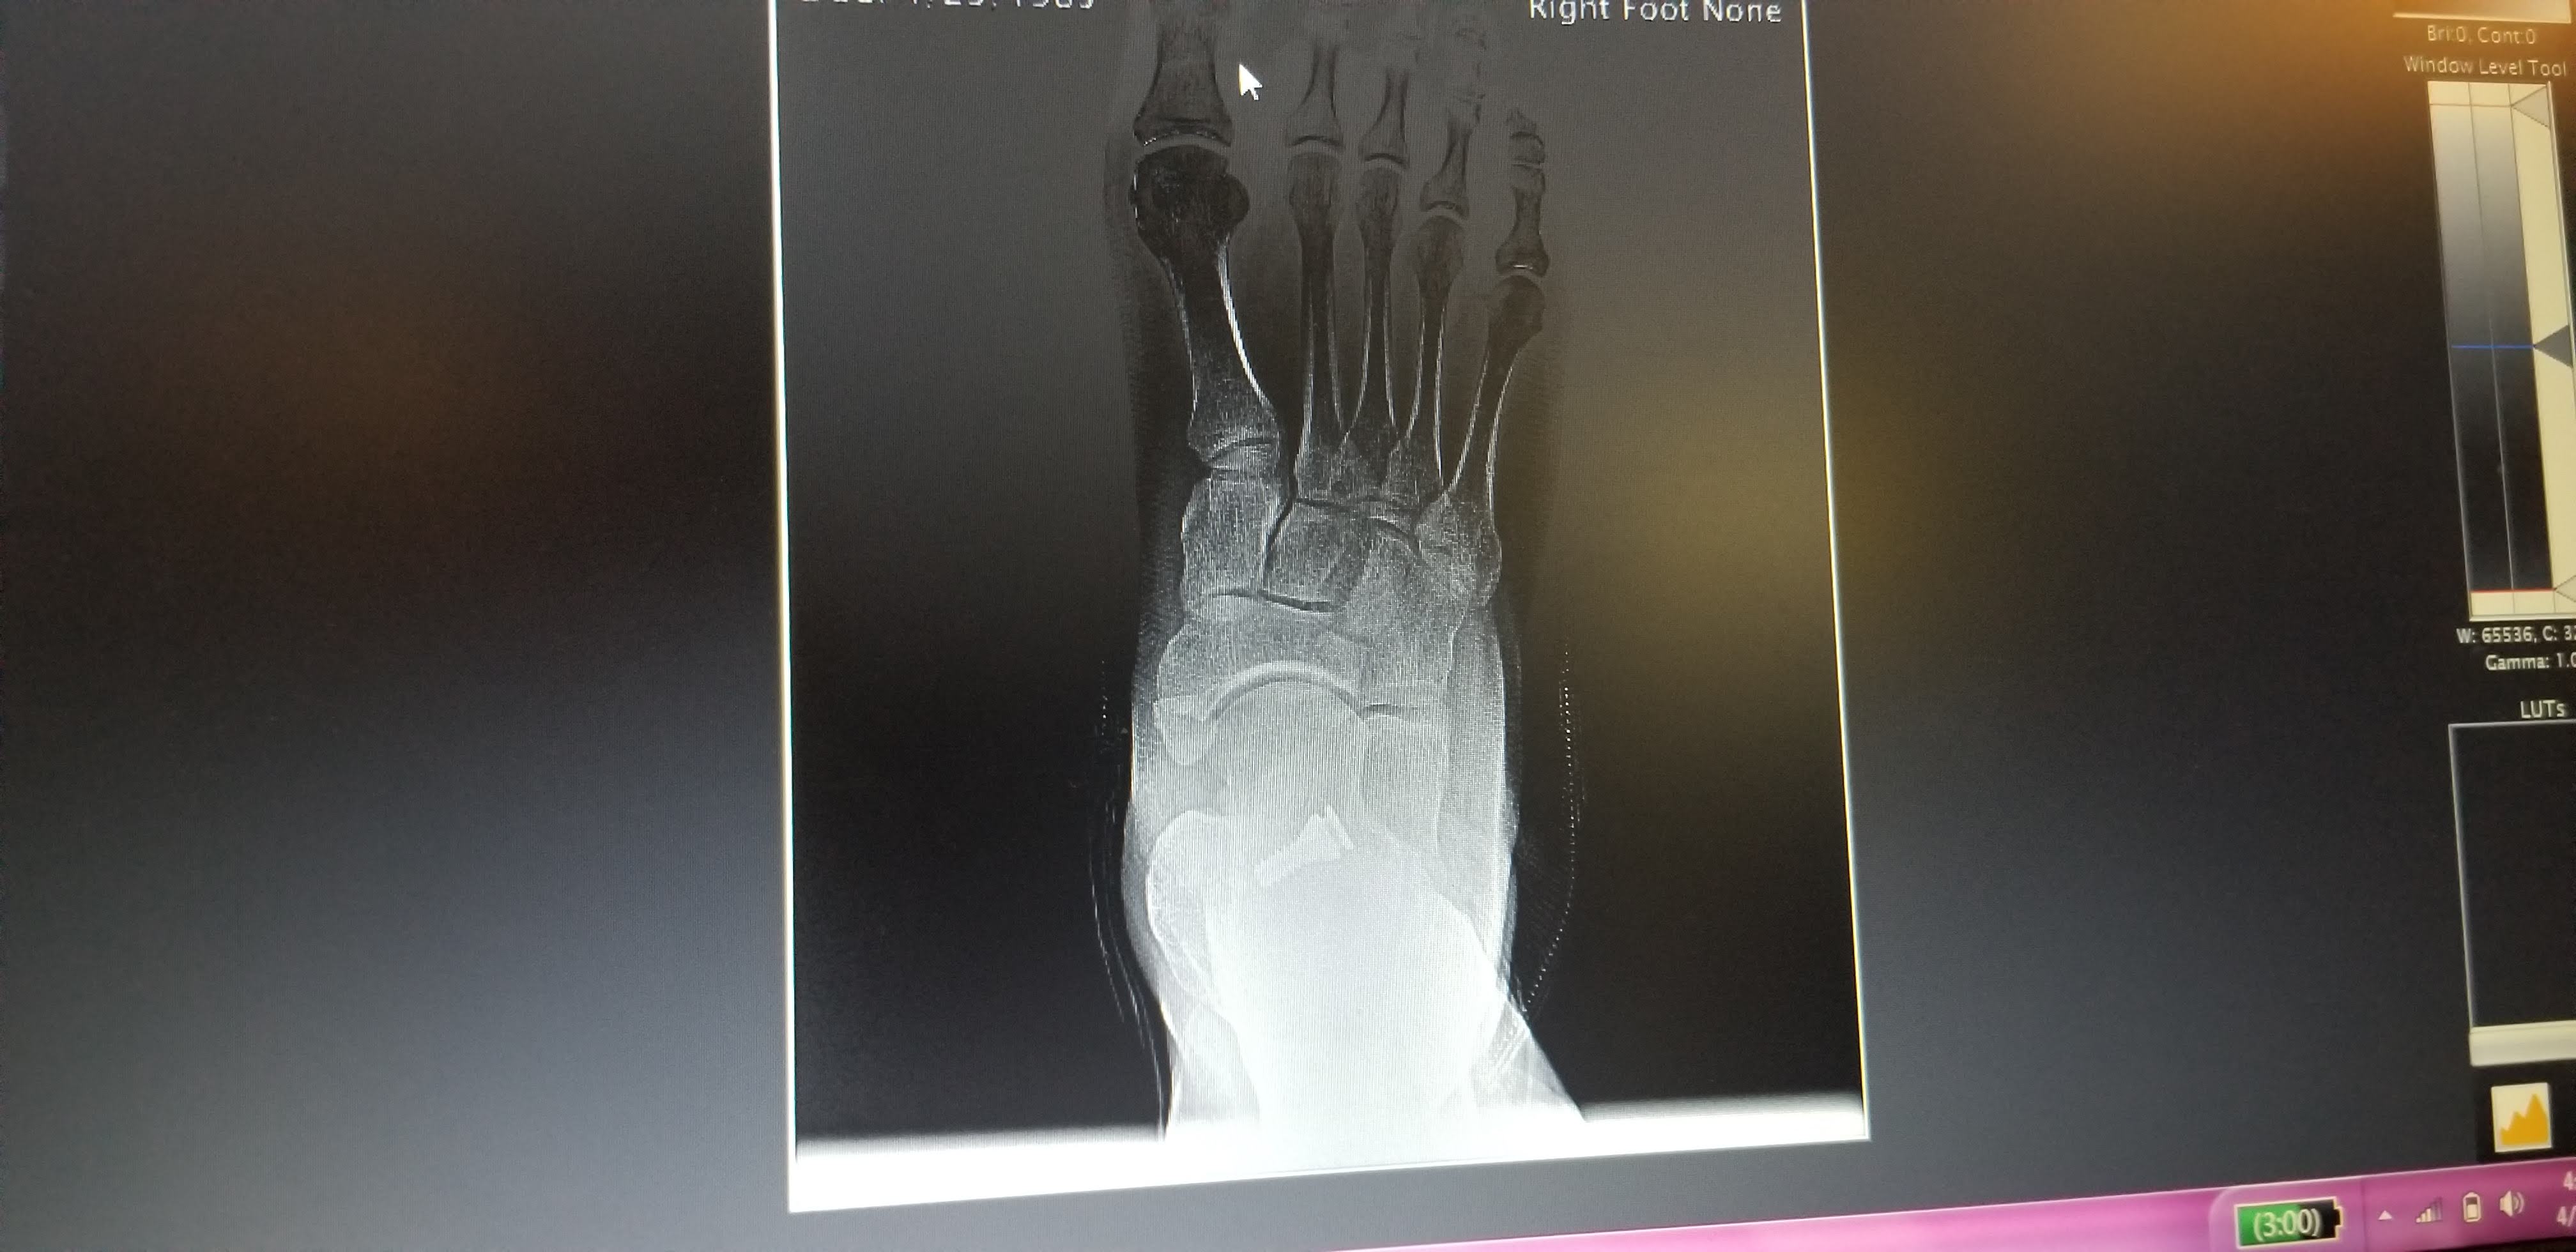

I went in on Tuesday, April 2nd, and had my right foot X-rayed. Unfortunately, the implant had backed out considerably since the day of the procedure.

It was still in the joint far enough to be having a beneficial effect, but it was well out of place from where it needed to be to provide the best result. After some discussion we decided that it would be best to try to re-seat the implant properly, both so that it would be more effective and so that it would be less likely to back out even further and eventually become ineffective. The left foot surgery scheduled for the following week became a right foot re-do surgery on the same day, and we decided to delay the left foot surgery indefinitely until we see how the right goes.